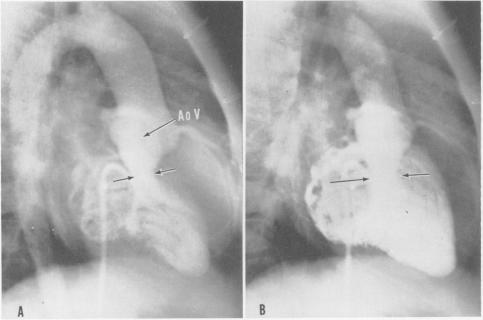

Surgical treatment of idiopathic hypertrophic subaortic stenosis: technic and hemodynamic results of subaortic ventriculomyotomy.

Ann Surg. 1961 Aug;154(2):181-9. doi: 10.1097/00000658-196108000-00003.